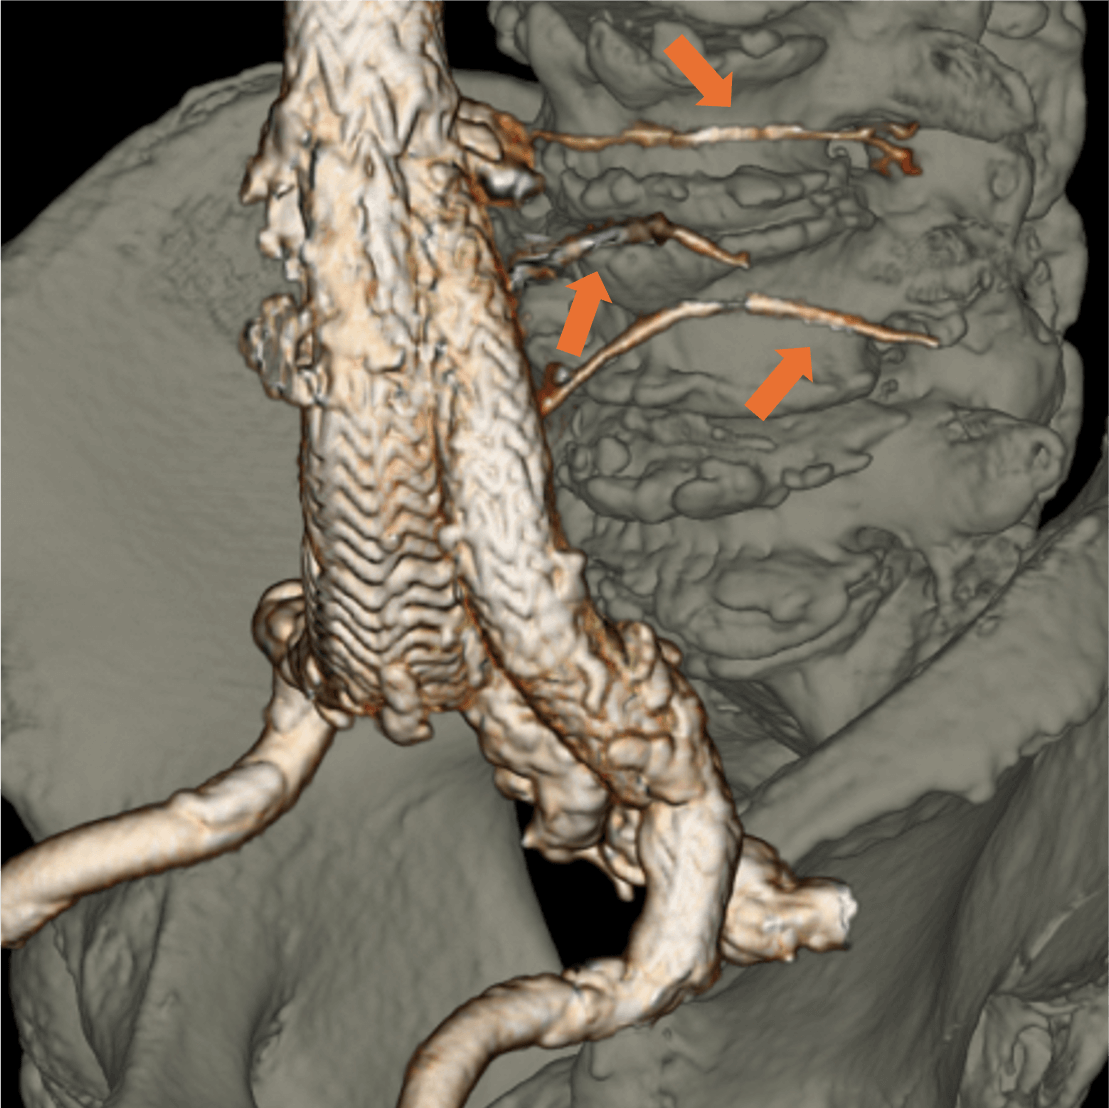

症例は80代男性。7年前に腹部大動脈瘤と右総腸骨動脈瘤に対しEVAR、2年前に腹部大動脈瘤のエンドリークに対し、下腸間膜動脈からコイル塞栓を行っている。動脈瘤が拡大傾向であったため、超音波検査が行われ、エンドリークが疑われた。評価と治療方針決定が必要と判断されたが、腎機能障害があったため入院での造影CTが計画された。

当該疾患の診断における造影CTの役割

CT技術や撮像プロトコル設定について

当院で使用されているCTは256列でのDual energy CTの撮影が可能なGEヘルスケア社のRevolution CTである。従来のSingle energy CTは1種類の管電圧を使用し、1種類のX線エネルギーを使用した撮像を行うが、本機種では高管電圧と低管電圧の2種類の異なる管電圧からそれぞれのX線エネルギーを使用した撮像が可能である。それにより、高画質かつ高コントラストの水密度画像とヨード密度画像が作成可能で、Deep learningを用いて解析を行うことでノイズの低減されたCT画像を再構成できる。本症例のようにTypeⅡエンドリークでは微小な血管が関与している場合があり、その検出と詳細な血管走行の確認において高コントラストかつ高画質の画像が求められ、Dual energy CTは有用である。